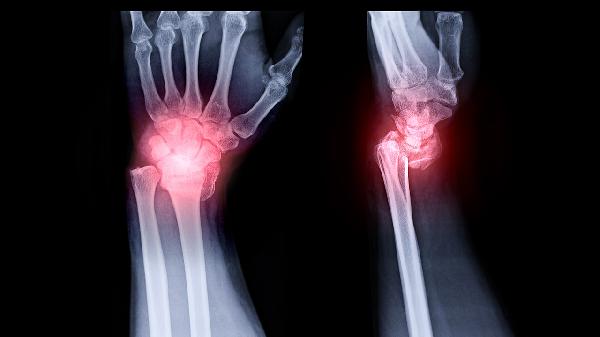

1、普通X线摄影:

普通X线摄影是最基础的X线检查技术,利用X射线穿透人体组织后在胶片上形成影像。该技术操作简便、成本较低,适用于胸部、骨骼等部位的初步筛查。检查时患者需保持特定体位,由技师调整曝光参数获取图像。成像后需暗室冲洗胶片,影像对比度与分辨率受限于传统胶片技术。常见应用包括骨折诊断、肺部感染筛查、异物定位等。